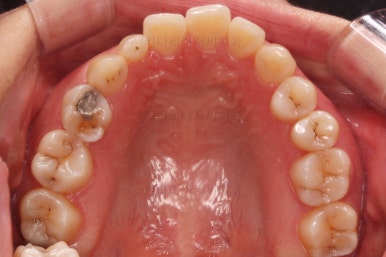

초진 시 입안의 모습인데요.

왜 그런지 비밀이 풀리는 것 같죠?

윗니는 한 쪽이 치아 2개가 결손이면서 유치가 하나 남아있고요.

아랫니는 한 쪽은 1개, 반대편은 2개 치아가 결손이었습니다.

도합 5개의 치아가 결손이었는데요.

결손 위치의 갯수가 위아래 좌우 다 달라서 중앙선이 맞을래야 맞을 수가 없는 상황이었죠.

결손치아 주위 치아들은 쓰러지고 비틀어져 있어서 장기적으로 좋지 못한 상황이었고요.

좀 더 디테일하게 윗니 작은 앞니 1개가 왜소치아라서 치아 크기도 맞지 않은 상황이었습니다.